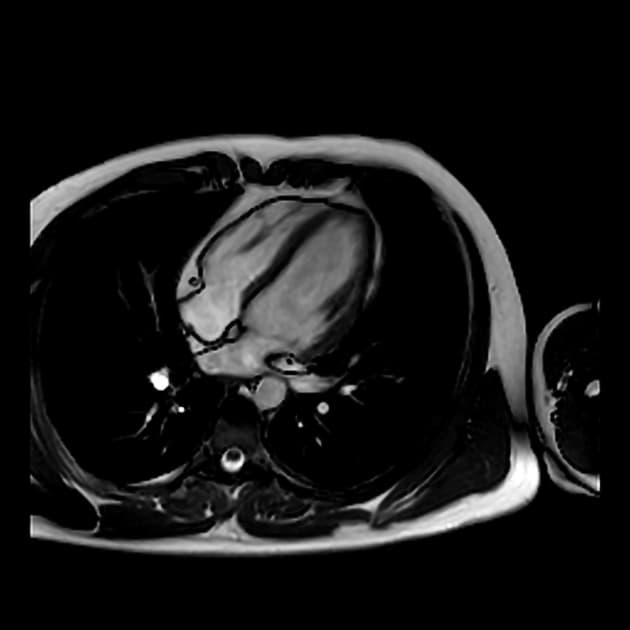

Short axis Cine SSFP

MRI•Short axis Cine SSFP•1 / 25

- Không thấy hình ảnh (no evidence of) vỡ thất, nhưng hình ảnh động (cine images) cho thấy thành trước giữa thất trái bị rối loạn vận động (dyskinetic), phồng ra ngoài trong thì tâm thu.

- Trên hình STIR, đoạn cơ tim tổn thương tăng tín hiệu (hyperintense), phù hợp với phù (edema).

- Không thấy huyết khối (thrombus) trên hình gadolinium sớm, và không thấy tăng quang cơ tim (myocardial hyperenhancement) trên hình gadolinium muộn.

- Có tràn dịch màng ngoài tim lượng nhỏ (small pericardial effusion).

- Phân suất tống máu thất trái (left ventricular ejection fraction) tính được nằm trong giới hạn thấp bình thường (không hiển thị).